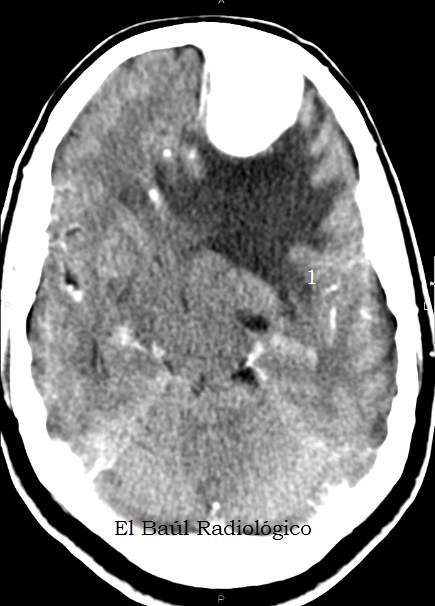

IMÁGENES SIN CONTRASTE ENDOVENOSO

Todas las exploraciones de Tomografía Computarizada craneoencefálica deben realizarse primero sin contraste endovenoso. Y, dependiendo de los hallazgos encontrados, se repite el examen despues de administrar una dosis de contraste. Si no se hace así podemos llevarnos alguna sorpresa.

FIGURA 3) Más edema vasogénico digitiforme. ¿.....?

(More digitiform vasogenic edema. .....?)